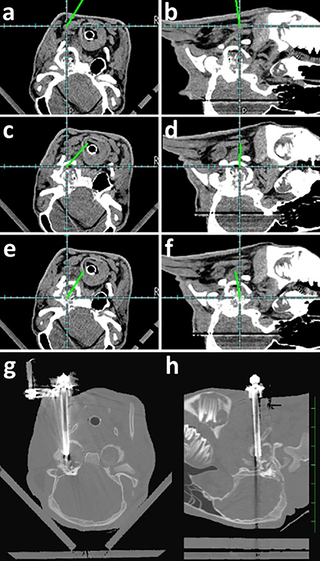

Utility of a freehand frameless navigation system in computed tomography-assisted ventral bulla osteotomy for otitis media in calves

Ventral bulla osteotomy has not been widely adopted for treating otitis media in calves due to its prolonged surgical duration (>1 h), high surgical invasiveness, and challenges in application for bilateral cases. This study aimed to evaluate the utility of a…